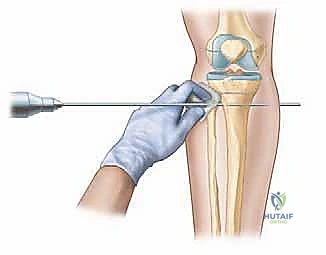

3. فترة الكمون والشد (Latency & Distraction)

بعد الجراحة، ينتظر المريض حوالي أسبوع (فترة الكمون). بعدها يتم تعليم المريض أو أسرته كيفية تدوير مفتاح الجهاز لتباعد العظم. القاعدة الذهبية التي يطبقها الدكتور هطيف هي "الإيقاع والمعدل" (Rhythm and Rate)؛ غالباً يتم الشد بمقدار 1 ملم يومياً، مقسمة إلى أربع مرات (0.25 ملم كل 6 ساعات). هذا الإيقاع يمنع تمزق الأنسجة ويضمن نمو عظم قوي.